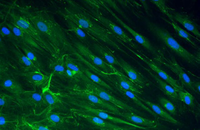

- Differentiation of cultured cells into different cell lines

- Confirmation of the nature of differentiated cells by ICC method

- Tracking of transplanted cells